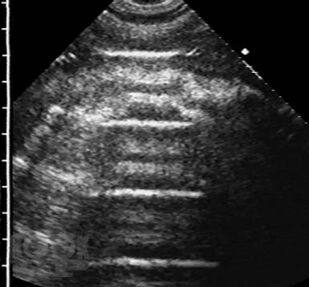

В учебном пособии в практическом аспекте изложены вопросы ультразвуковой диагностики воспалительных заболеваний легких: приведены методика исследования и нормальная эхографическая картина грудной клетки, подробно освещены ультразвуковая семиотика и дифференциальная диагностика пневмоний, в том числе деструктивных, абсцессов и гангрены легкого, для каждого из них выделены диагностически значимые эхопризнаки. Впервые представлена эхосемиотика пневмоний в зависимости от степени тяжести воспалительной инфильтрации, а также абсцессов легкого в зависимости от эффективности спонтанного дренирования его полости бронхами. Пособие иллюстрировано большим количеством эхограмм, отображающих основные диагностические признаки рассматриваемых заболеваний.